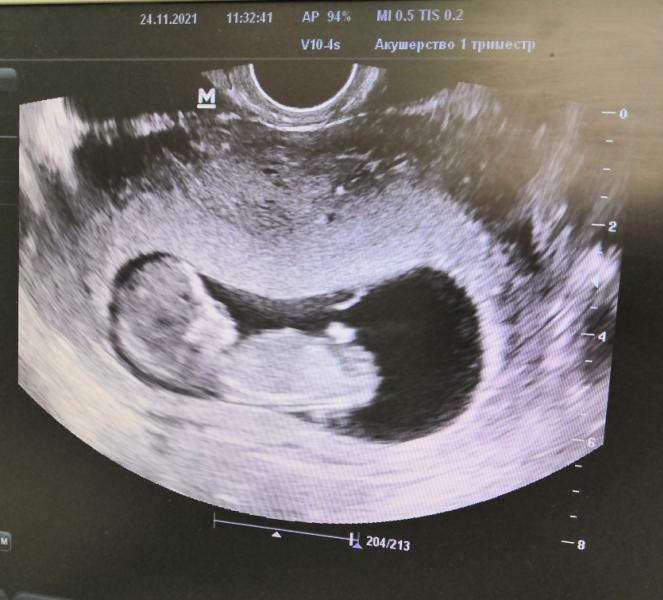

Сегодня нам 10 недель и 5 дней если вести счёт с первого дня последних критических дней😌

После приёма сходила на УЗИ (для своего спокойствия), по УЗИ нам 12 недель и 3 дня 😳 пошла обратно к гинекологу, показала рассказала и в итоге скрининг 1 декабря😌